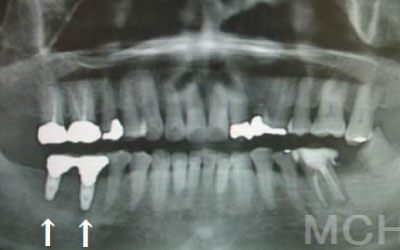

骨が薄い場合、そのままインプラントを行うのはお勧めできません。

ただし、事前に骨を増やす治療を行ったり、インプラントと同時に骨を増やす治療をすることで、インプラントは可能です。

しかし、事前にCTでしっかりと撮影し、三次元的に神経との距離を計測して治療計画を立てることで、心配は不要です。

また、当院では削りすぎを防ぐためのストッパーも使用しています。

1)インプラント治療を行う前に、骨の治療が必要かもしれません。

2)骨の治療から始めると、その分、治療期間が長くなります。

3)骨の治療は、通常のインプラント治療よりも難易度が高いため、経験の豊富な先生やインプラント認定医のいる歯科医院で治療を受けることをお勧めします。

4)骨の状況をしっかり把握するためにも、CT撮影が必須となります。